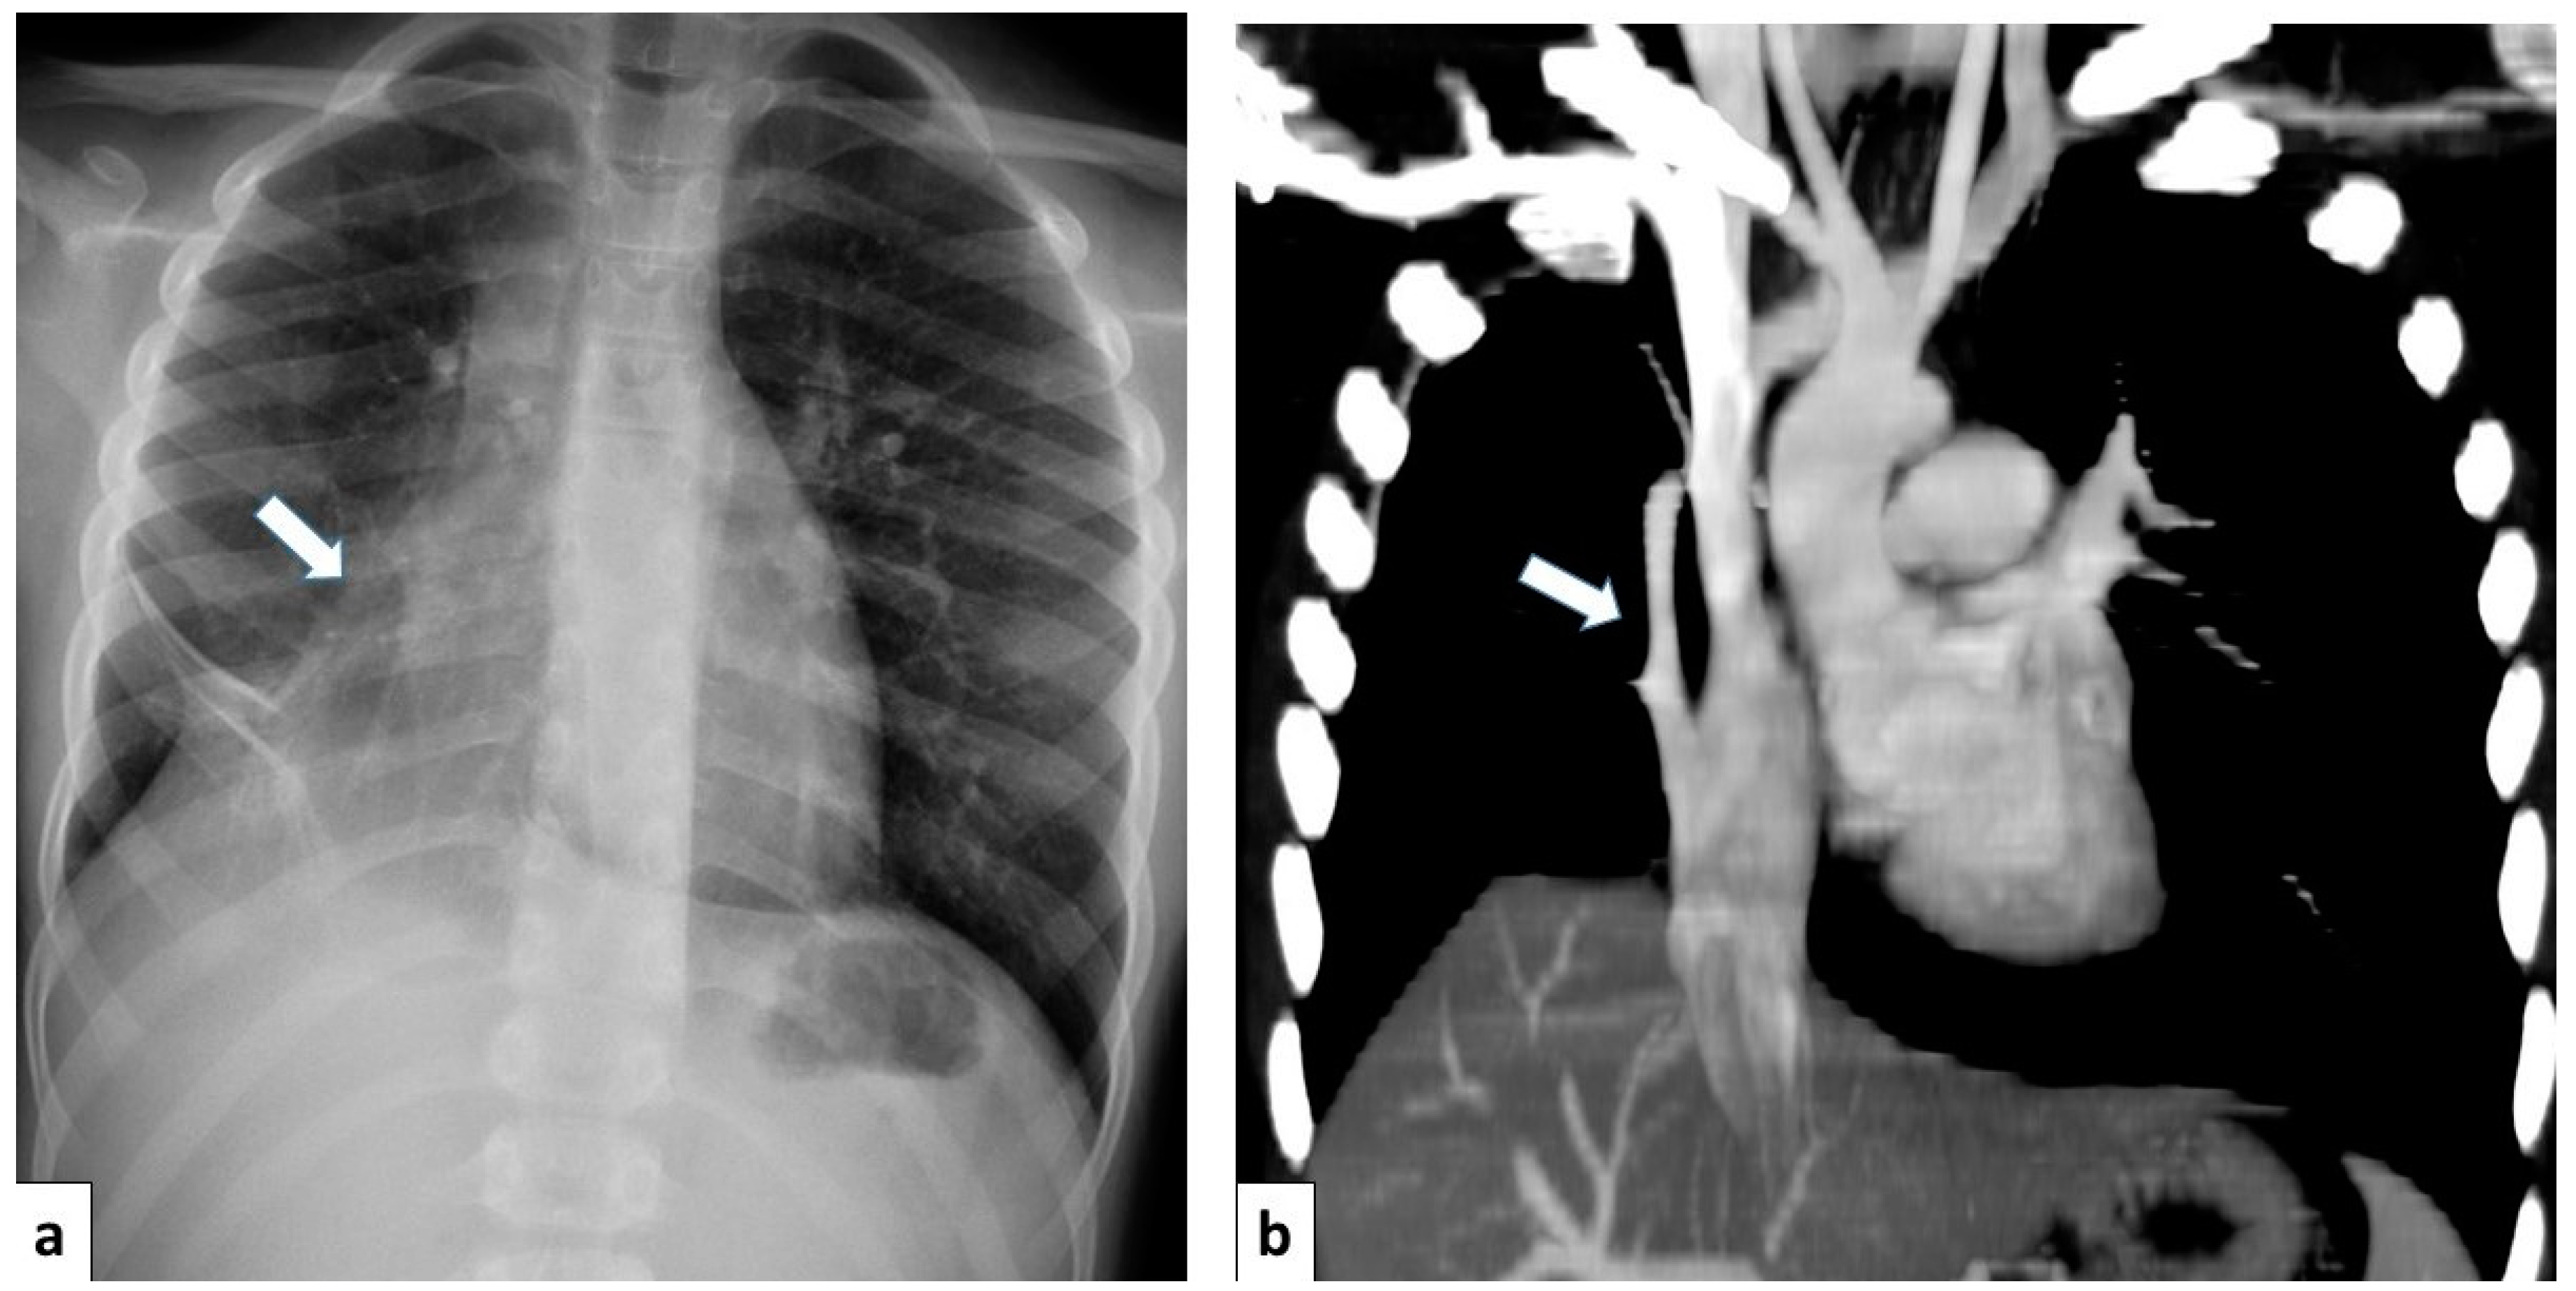

Chest radiography is a valuable initial imaging modality for pulmonary sequestrations. In up to 98% of cases, it demonstrates these malformations as circumscribed lung masses predominantly involving the lower lobes, with a left-sided predilection [15,35]. Additionally, the anomalous systemic arterial supply may sometimes be visualized on plain radiographs [4]. In cases of intra-lobar sequestration, repetitive infections can predispose a patient to liquefaction necrosis, manifesting radiographically as a mainly cystic lesion that may contain air-fluid levels [8,15] (Figure 13).

Figure 13.

Chest radiograph of a 17 year old boy shows focal lung masses within the left lower lobe with microcystic appearance due to recurrent infection, suggesting an intra-lobar sequestration (arrow).

CT angiography with 3D reconstruction serves as a highly informative tool for identifying anomalous feeding arteries and drainage veins for differentiating between intra- and extra-lobar sequestration (Figure 14 and Figure 15). The CT appearance of the lesion ranges from a homogeneous soft tissue mass within the parenchyma (Figure 16) to a cystic lesion containing air or fluid, which can coexist in hybrid forms [15,37].